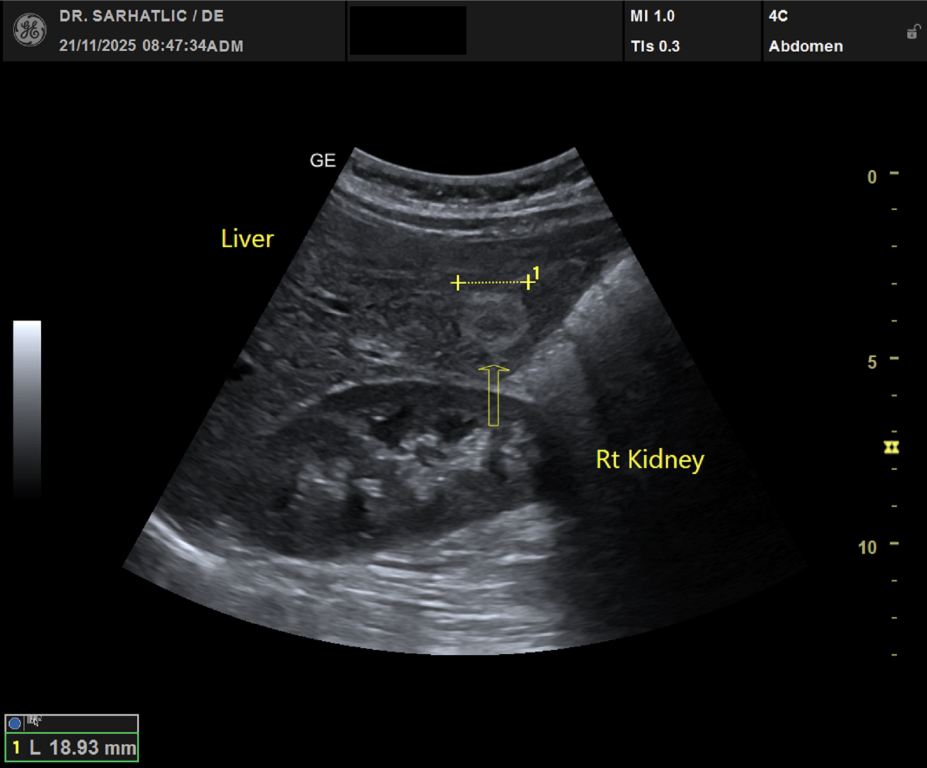

- Ultraschall aller inneren Organe (z. B. Leber, Bauchspeicheldrüse, Nieren, Prostata, Schilddrüse)